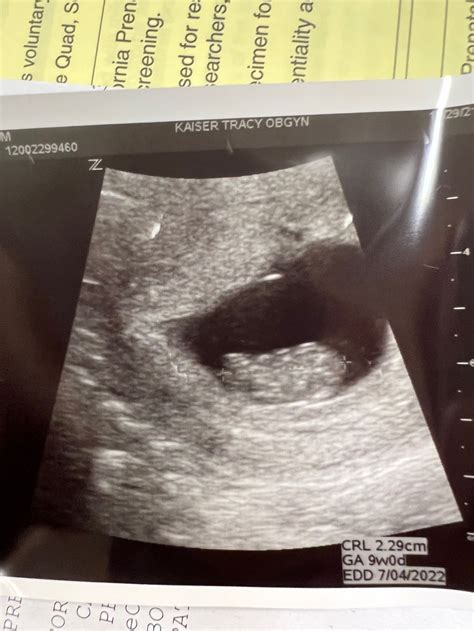

A 9 weeks pregnant ultrasound is typically performed to assess the baby's growth and development. At this stage, the ultrasound can provide detailed images of the fetus, allowing healthcare providers to measure the baby's size, check for a heartbeat, and evaluate the overall health of the pregnancy. This scan is usually done transabdominally, meaning the ultrasound probe is moved over your belly, or transvaginally, where the probe is inserted into the vagina for a clearer view.

• Size: Your baby is about the size of a grape, measuring approximately 0.63 inches (1.6 centimeters) in length and weighing around 0.07 ounces (2 grams).

• Heartbeat: The baby's heartbeat is usually detectable by ultrasound, and it may be visible as a rapid fluttering.

• Crown-Rump Length (CRL): The measurement from the top of the head to the bottom of the buttocks, which helps to estimate the baby's age and growth.

📝 Note: The crown-rump length is a crucial measurement that helps healthcare providers determine the baby's gestational age and ensure that development is progressing normally.